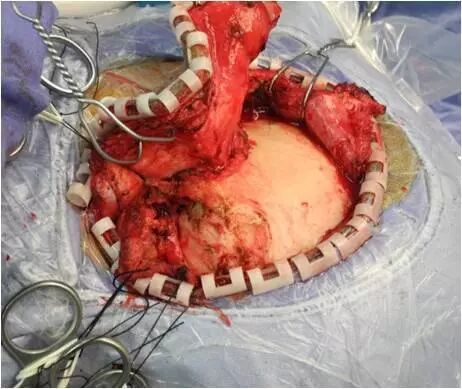

坐位听神经瘤切除术视频(摘自鲍教授上述讲课)

鲍遇海教授:坐位听神经瘤切除术

听神经瘤

手术体位个性化选择